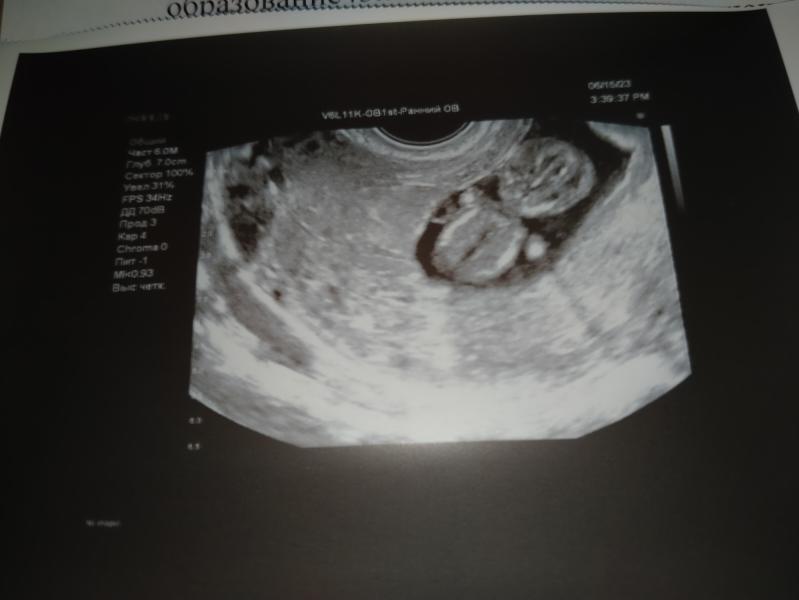

Была сегодня на УЗИ, у нас все отлично 🥰🥰🥰

Делаем ставки ,кто будет😂 потом обязательно отпишусь))))

Узнала пол. У нас мальчик 100%🩵